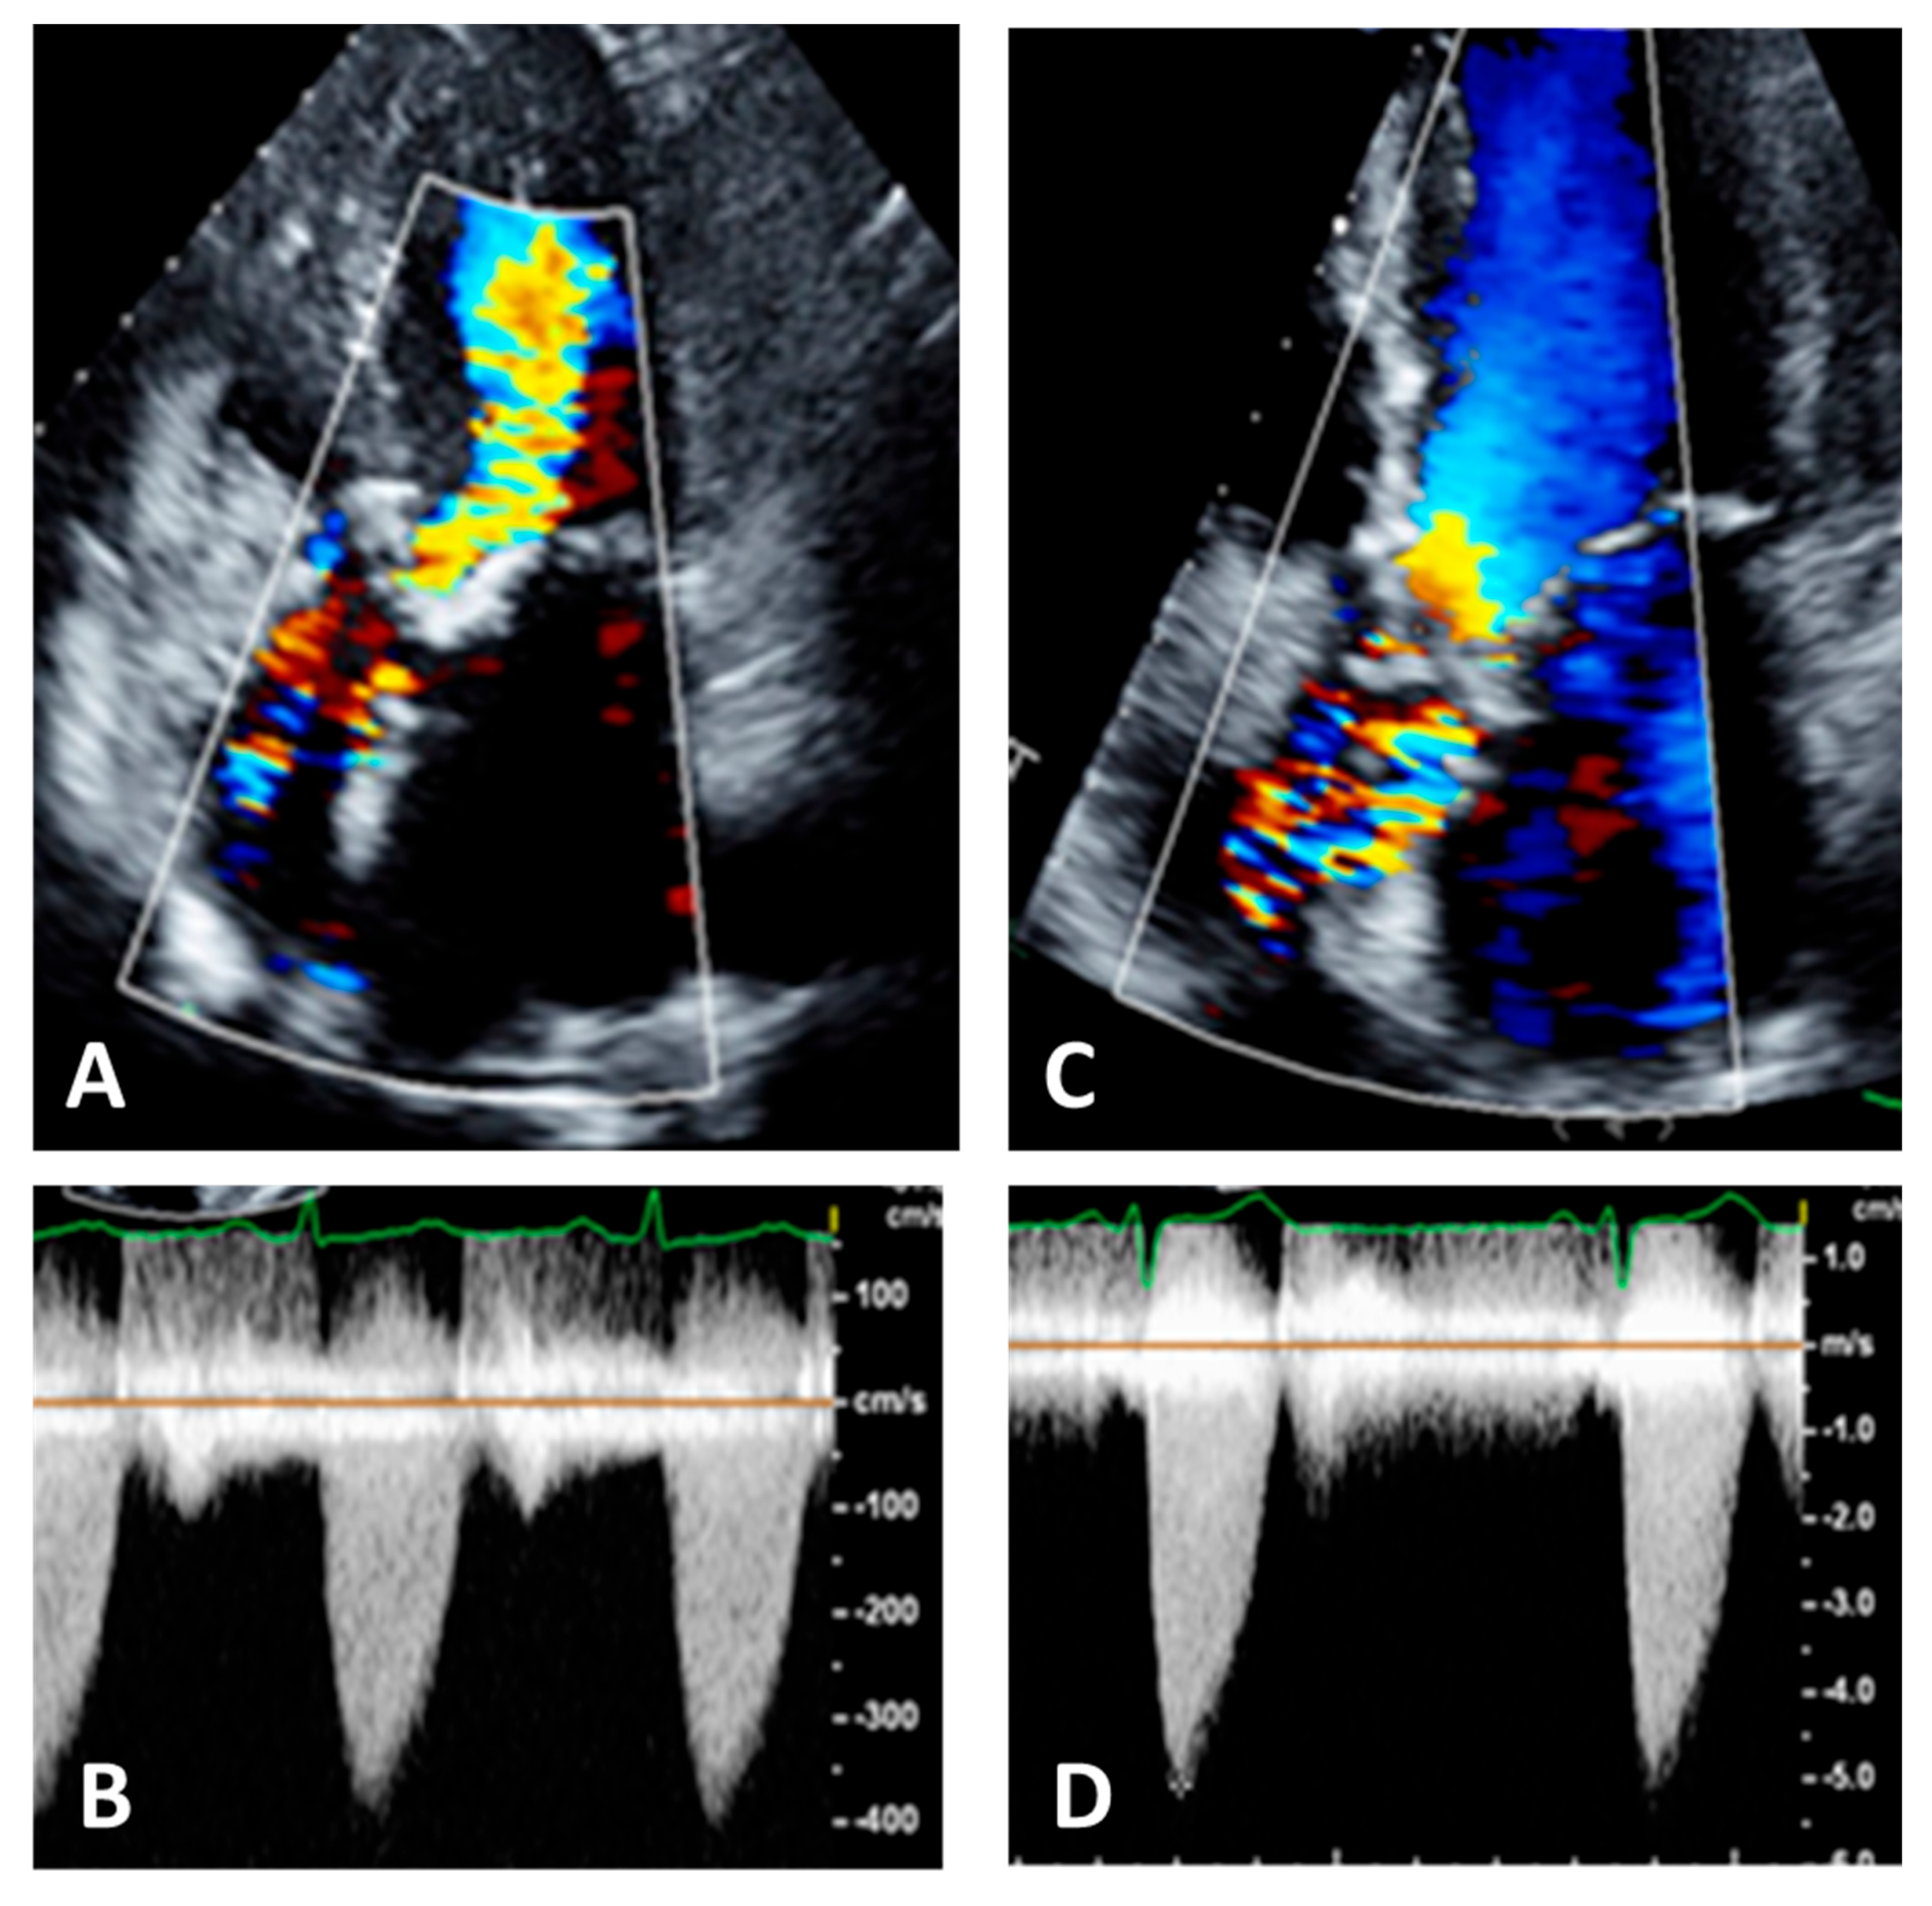

Pulsed Doppler. Pulsed Doppler represents blood flow velocities from a specific cardiac depth, with a depth of interest named sample volume. It is important to standardize the sample volume in your machine [21]. Usually, a sample volume length of 3–5 mm is recommended to obtain the best relationship between resolution and quality of the signal [21]. As pulsed Doppler uses the same piezoelectric crystals to send and receive sound waves, there is a maximum limit of the Doppler frequency that can be measured. If velocity is higher than the Nyquist limit, aliasing occurs, i.e., an apparent change in the direction of blood flow [21]. High pulse repetition frequencies are not suggested because it has the drawback of including signals from each of the originated sample volumes. The gain and scale settings should be optimized in such a way that the entire curve can be seen. The machine operator must ensure that the Doppler signal is large enough to measure accurately the blood velocity in that specific cardiac depth; the velocity curve should be smooth and have a dense outer edge to be measured, and the small, fine, linear signals should be excluded. LVOT spectral Doppler velocity time integral (VTI) assessment with the sample volume in a wrong position or being too large, with too high gain or too high wall filter settings, low sweep speed, and baseline inappropriately low [22,41]. The LVOT VTI is recorded from an apical approach, using either an anteriorly angulated four-chamber view or positioning the sample volume of pulsed Doppler proximal to the region of blood flow acceleration in the LVOT (Figure 8).

When measuring, it is important to search not only the highest velocities but also note which acoustic window yields this peak AS jet velocity [29,45]. Attention should be paid to identifying the highest velocity, i.e., aliasing, seen at color Doppler, not only at valve level but also in the ascending aorta so that the continuous beam should be placed as parallel as possible to this flow (Figure 9).

Figure 8. Left panel: underestimation of left ventricular outflow velocity time integral due to increased angulation between the sample volume and the direction of blood flow. Right panel: reduction in the angle results in an increase in the left ventricular outflow tract velocity time integral.

Figure 9. Panel (A): five chamber view. Color Doppler is not well visualized in ascending aorta, Panel (B); this results in an underestimation of the aortic velocities. Panel (C): the same patient with correct visualization of color Doppler in ascending aorta, Panel (D). This results in an increase and correct recording of aortic velocities.